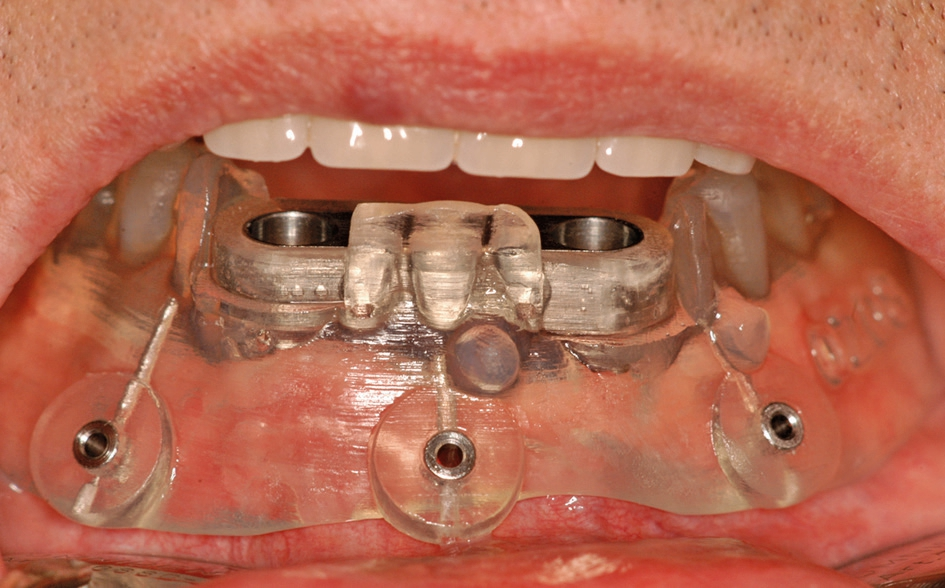

Abb. 6: Die SOS-Schablone wird durch die Gegenbezahnung (hier OK-Totalprothese) in zugebissenem Zustand auf dem Unterkiefer stabilisiert, bevor sie mit den Pins befestigt wird.